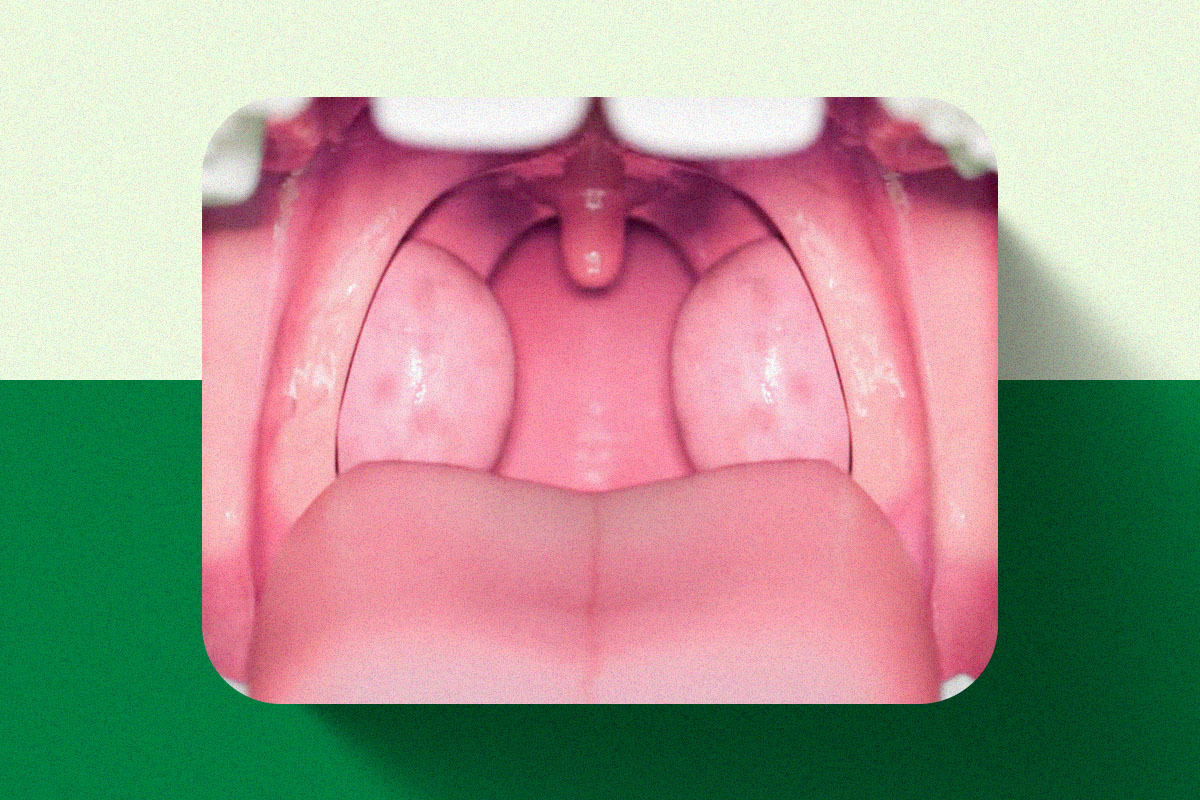

As amígdalas são duas estruturas localizadas no fundo da garganta, uma de cada lado.

Amígdalas muito aumentadas

Quando o aumento das amígdalas provoca dificuldade para respirar, engolir ou falar.